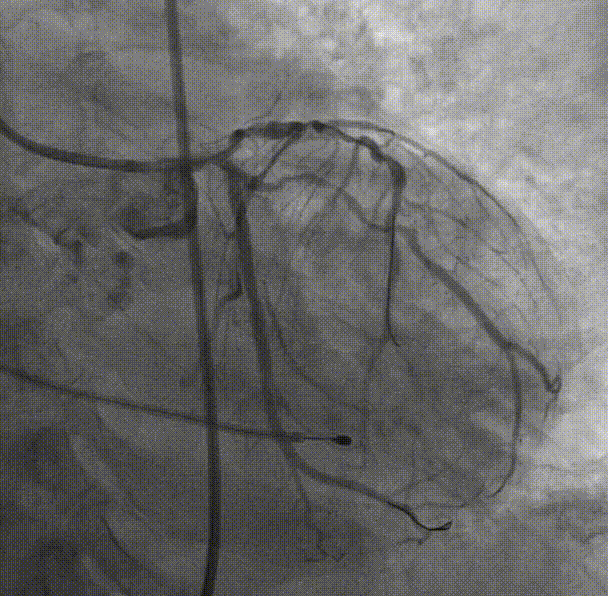

CAG:左主干前三叉真性分叉病变,病变钙化明显,左主干末端狭窄约85%,前降支近段狭窄70-80%,中段长弥漫狭窄60-70%,回旋支开口狭窄60-70%,近中段狭窄80-90%;右冠近段狭窄80-90%,中段狭窄85%,远段狭窄50%。考虑患者胸痛症状可能为冠心病+AS共同作用,以及患者冠脉病变钙化严重,予以PCI+TAVR一站式处理。

右冠中段开口予Balloon Trek2.5*15mm预扩;于中段至开口依次植入Integrity stent3.5*30mm;Integrity stent3.5*22mm;支架内予Balloon NC Trek3.5*12mm后扩。

回旋支中段予Balloon Trek2.5*15mm预扩,回旋支近中段植入3.0*36mm支架;支架内予Balloon NC Trek3.5*15mm后扩;左主干-前降支近段病变予Balloon Trek2.5*15mm预扩;于左主干-前降支近段植入Integrity Stent3.0*26mm;前降支支架内予Balloon NC Trek3.5*12mm后扩,回旋支开口无受压,远端血流TIMI3级。

复查冠脉造影结果满意。